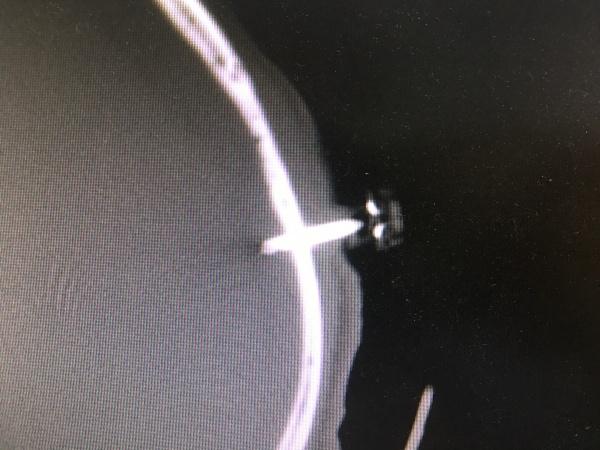

手术过程还是很顺利,引流通畅,术后复查CT:

可见脑组织明显复位,血肿大部分引流,观察穿刺针深度及侧孔情况,予以拔出3mm-5mm左右,一天后拔除血肿穿刺针。